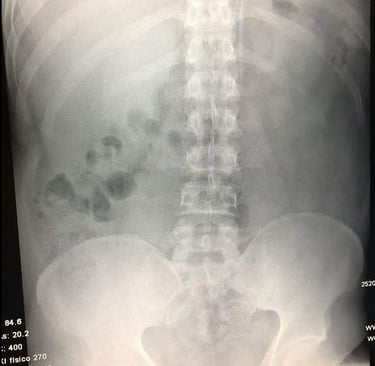

Si el dolor de espalda persiste, es importante acudir a un especialista para determinar su causa exacta. Algunos de los diagnósticos más comunes incluyen:

Si el dolor de espalda es persistente o interfiere con tu rutina diaria, es importante acudir con un especialista. A través de una evaluación clínica y estudios de imagen, se puede identificar la causa del problema y diseñar un tratamiento adecuado para aliviar el dolor de manera efectiva.